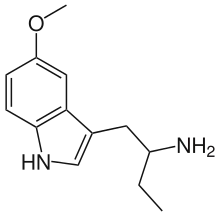

List of substituted α-alkyltryptamines

α-Alkyltryptamines are a group of substituted tryptamines which possess an alkyl group, such as a methyl or ethyl group, attached at the alpha carbon, and in most cases no substitution on the amine nitrogen.[17][18][19] α-Alkylation of tryptamine makes it much more metabolically stable and resistant to degradation by monoamine oxidase, resulting in increased potency and greatly lengthened half-life.[19] This is analogous to α-methylation of phenethylamine into amphetamine.[19]

Many α-alkyltryptamines are drugs, acting as monoamine releasing agents, non-selective serotonin receptor agonists, and/or monoamine oxidase inhibitors,[20][21][22][23] and produce psychostimulant, entactogen, and/or psychedelic effects.[17][18][19] The most well-known of these agents are α-methyltryptamine (αMT) and α-ethyltryptamine (αET), both of which were used clinically as antidepressants for a brief period of time in the past and are abused as recreational drugs.[18][19] In accordance with its action as a dual releasing agent of serotonin and dopamine, αET has been found to produce serotonergic neurotoxicity similarly to amphetamines like MDMA and PCA, and the same is also likely to hold true for other serotonin and dopamine-releasing α-alkyltryptamines such as αMT, 5-MeO-αMT, and various others.[24]

5-MeO-αMT | 1-(5-methoxy-1H-indol-3-yl)propan-2-amine | 1137-04-8 |

5-MeO-αET | 1-(5-methoxy-1H-indol-3-yl)butan-2-amine | 4765-10-0 |

N,N-Dimethyl-5-MeO-αMT (5-MeO-α,N,N-TMT) | (2-(5-methoxy-1H-Indol-3-yl)-1-methyl-ethyl)dimethylamine | 101831-90-7 |